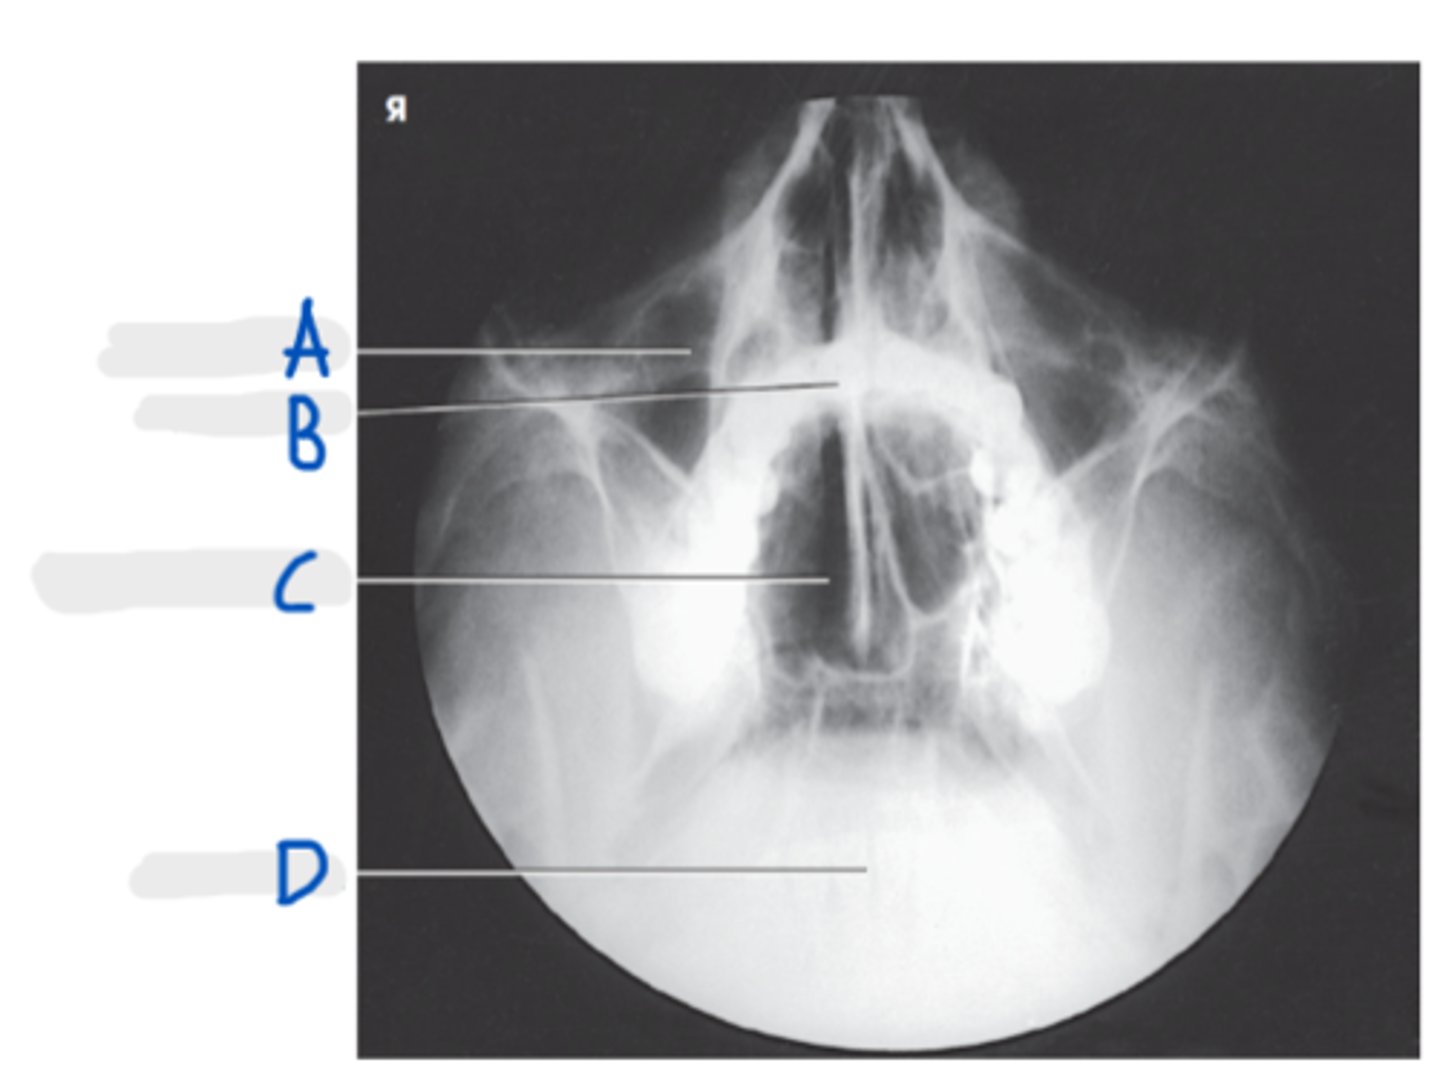

Frontal sinus

A

Crista galli

B

Superior orbital margin

C

Superior orbital fissure

D

Ethmoid sinus

E

Petrous ridge

F

PA Skull

What projection is this?

Orbits fill the petrous ridges

How can we tell this is a PA skull?

CR to exit the nasion

What is the CR for a PA or PA axial (Caldwell) skull?

OML perpendicular to IR

What line should be perpendicular to the IR for a PA or PA axial (Caldwell) skull?